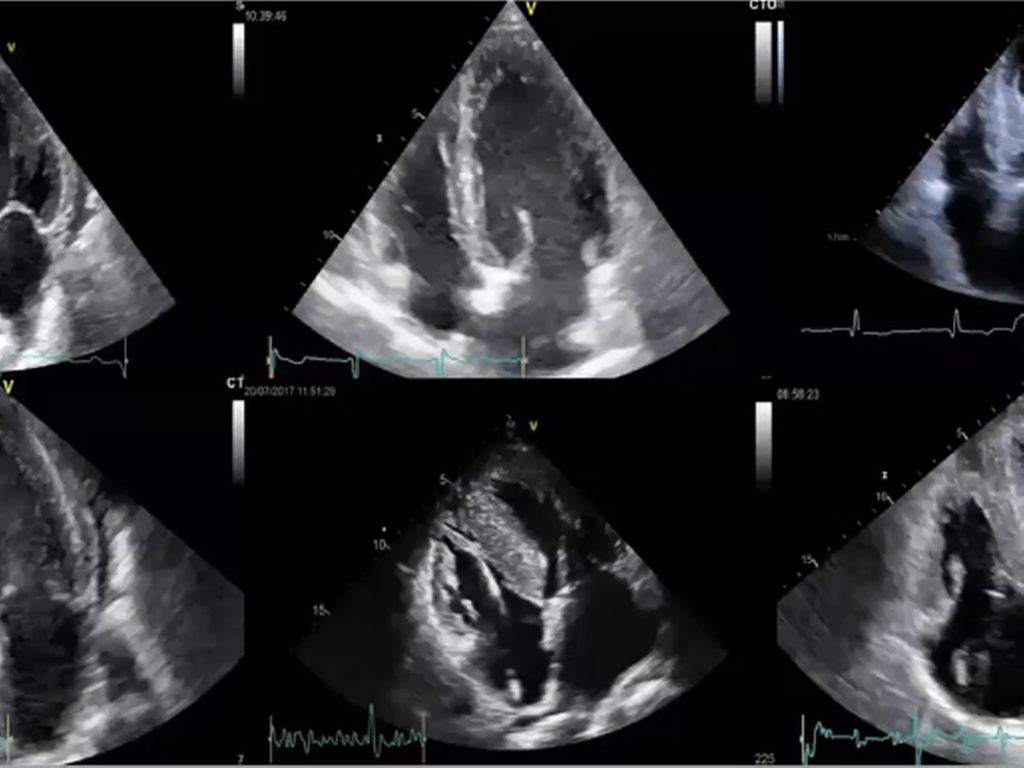

Multiples Myelom: Diagnostik, Erstlinientherapie und Therapie des ersten Rezidivs